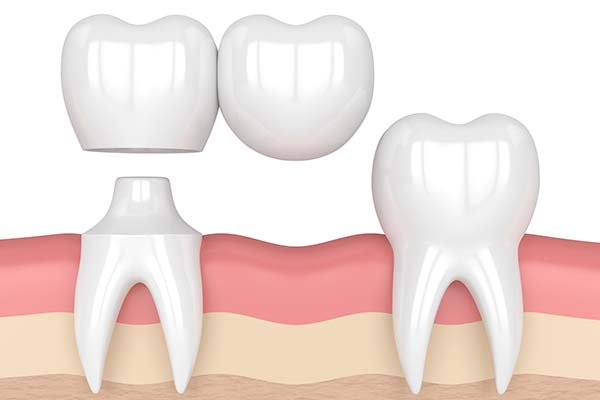

Dental bridges span gaps where teeth have been lost, and we can think of them as a series of linked crowns.

The image depicts a dental bridge with adjacent crowns

Before a dental bridge can be made, supporting teeth, need to be prepared by making them a little smaller so the crown anchor points can fit over them. After this procedure, we will take an impression to provide an exact mould for the technicians to manufacture the prosthetic.